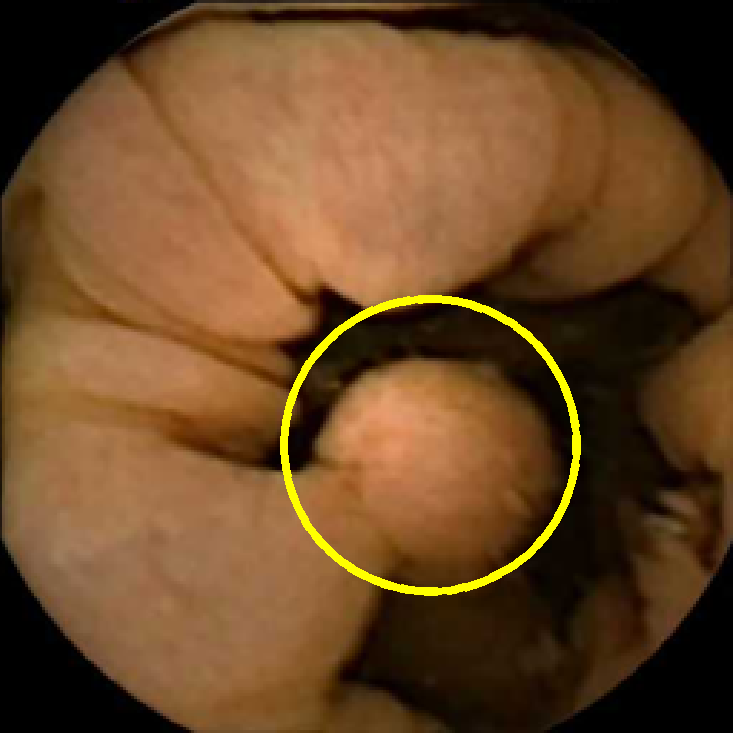

In Figure 5 we show the circles of radius corresponding to the features that were correctly classified as polyps by (29). We observe that the classifier was able to identify the polyps of a variety of shapes even in the presence of small amounts of trash liquid (first row) or when the polyps are located next to mucosal folds (rows two to four in column (c)).